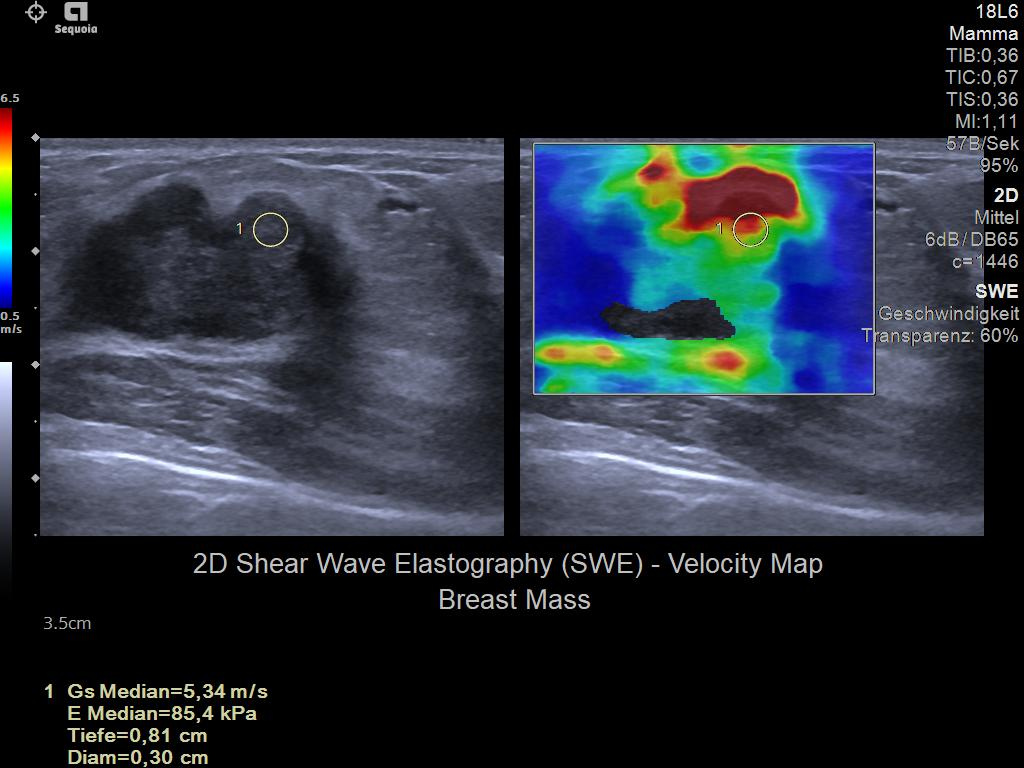

- Next Gen 2D-SWE for greater sensitivity in detection and visualization of malignant breast lesions.